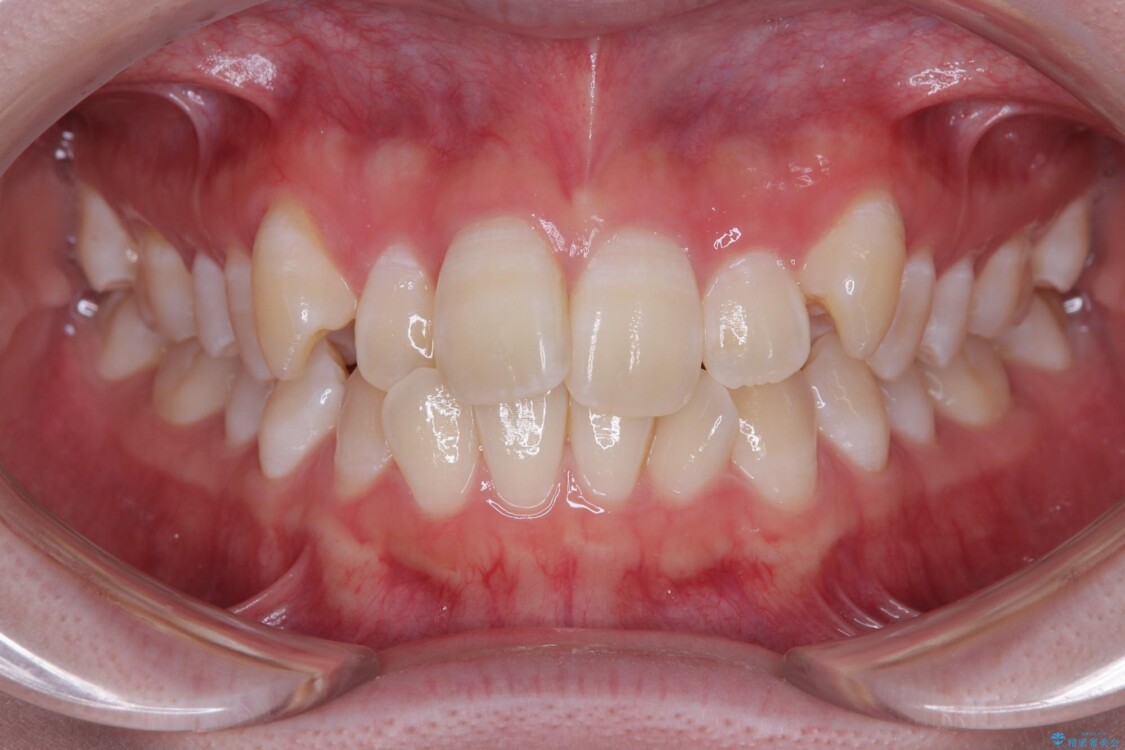

「前歯のデコボコ(叢生)をきれいに整えたい」とのことでご来院されました。

治療前

• 【モニター】前歯のデコボコをスッキリ解消!目立ちにくいワイヤー矯正でスピーディに治療完了 治療前画像